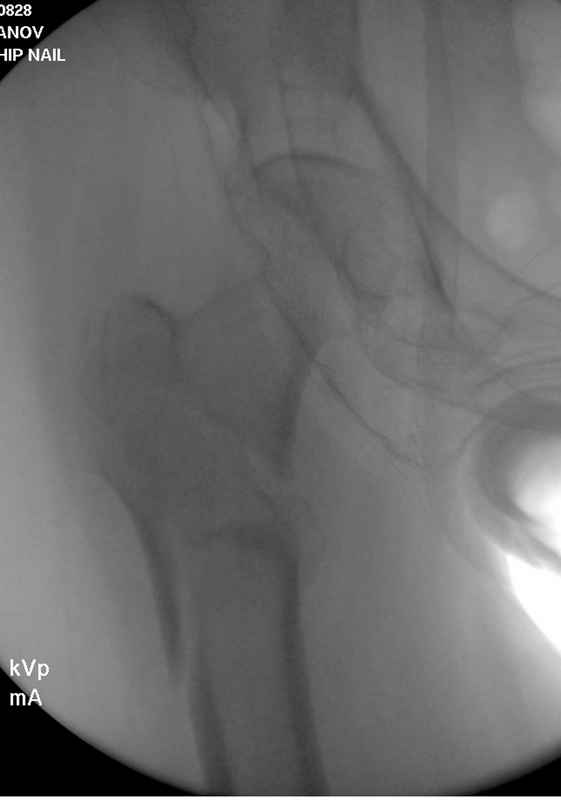

Здесь пара случаев фиксации похожих переломов:

первый высокоэнергетическая травма 36 лет

Здесь 83 года, травма в результате падения